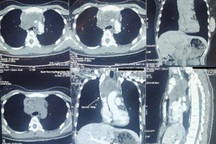

Ảnh chụp phim của bệnh nhân cho thấy có tổn thương đông đặc nhỏ phổi phải (Ảnh: BS).

Nhờ phát hiện sớm bệnh, bà V. được điều trị kịp thời với triệu chứng cải thiện hoàn toàn sau 1 tuần dùng thuốc. Ảnh chụp phim phổi sau đó của bệnh nhân không còn thấy tổn thương.

Một trường hợp bị tổn thương phế nang thùy dưới phổi phải (Ảnh: BS).